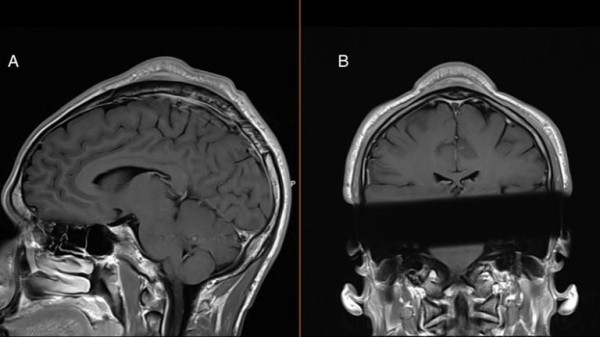

Medics ruled out cancer and other potential diseases before diagnosing a “headspin hole”.

“It manifests as a fibrous mass on the scalp,” medics said.

“It is characterised by hair loss, inflammation, numbness and sometimes formation of a lump on the scalp. In radiologic descriptions, the term ‘cone-head sign’ is used”, they wrote.